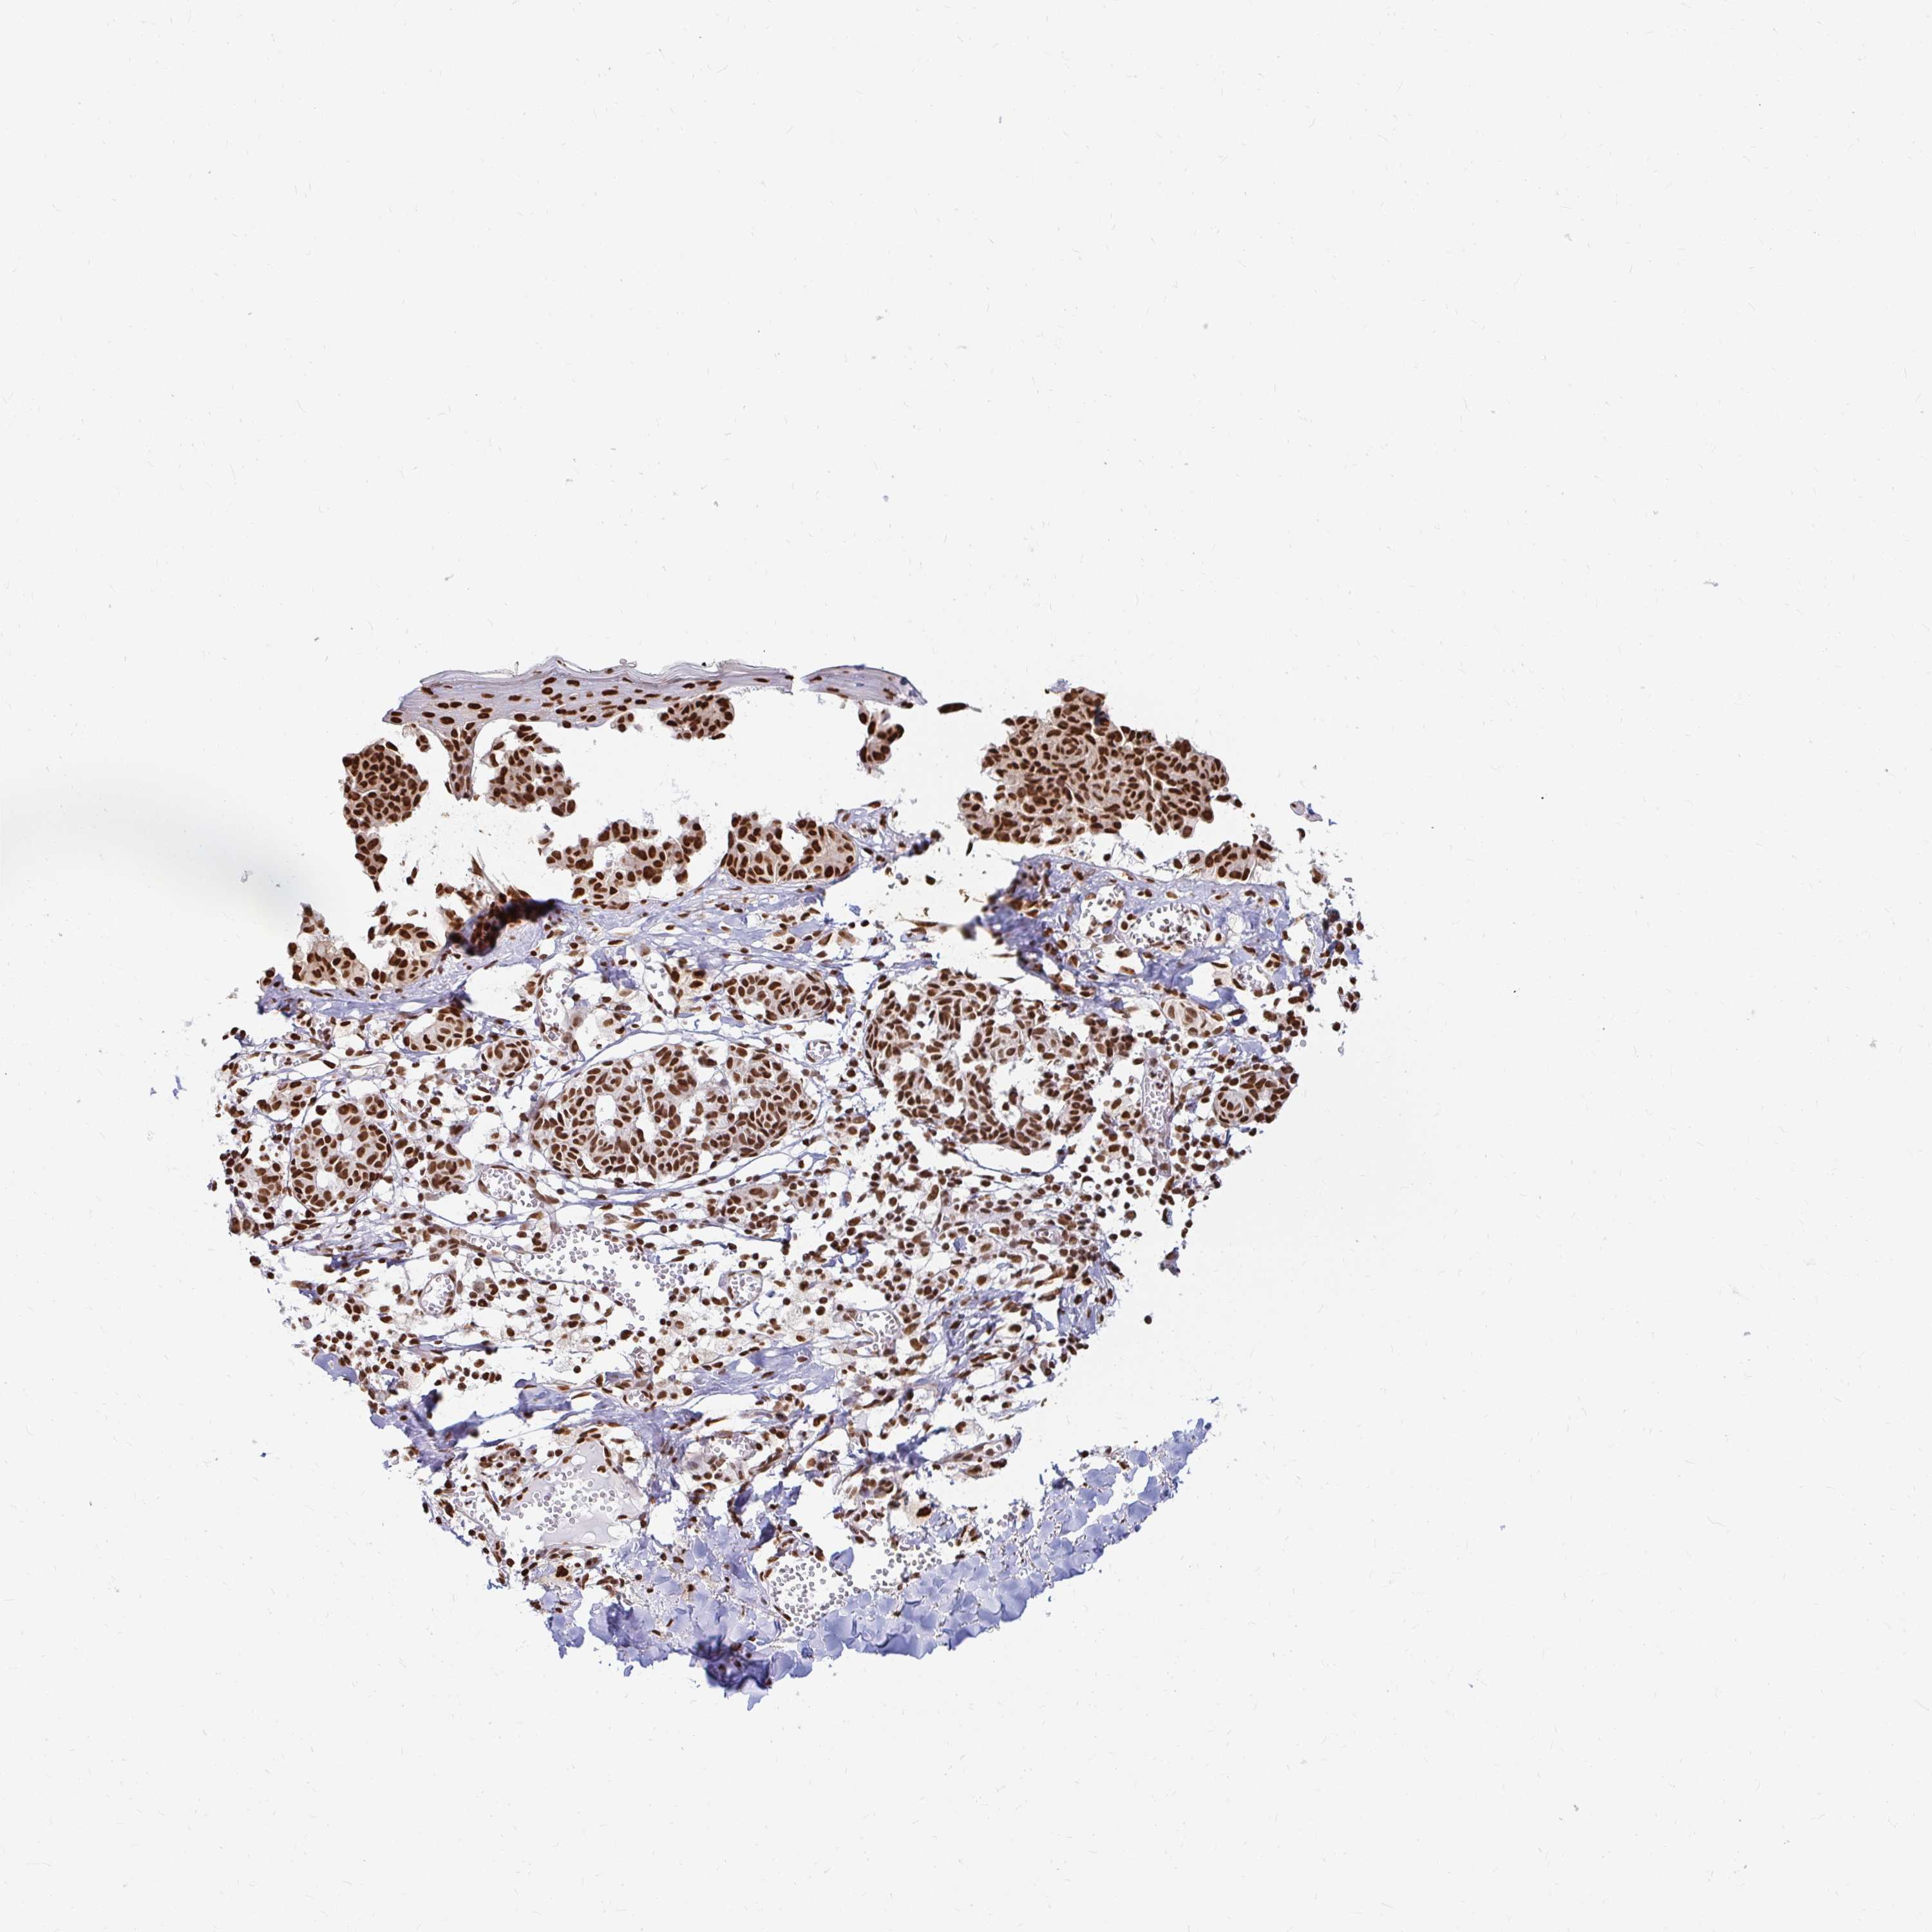

MELANOMA - Protein expressioni

A mouse-over function shows sample information and annotation data. Click on an image to view it in a full screen mode. Samples can be filtered based on level of antibody staining by selecting one or several of the following categories: high, medium, low and not detected. The assay and annotation is described here.

Note that samples used for immunohistochemistry by the Human Protein Atlas do not correspond to samples in the TCGA dataset.

Antibody stainingi

Antibody staining in the annotated cell types in the current human tissue is reported as not detected, low, medium, or high, based on conventional immunohistochemistry profiling in selected tissues. This score is based on the combination of the staining intensity and fraction of stained cells.

Each image is clickable and will lead to virtual microscopy that enables deeper exploration of all samples and also displays staining intensity scores, fraction scores and subcellular localization as well as patient and tissue information for each sample.

Antibody HPA041057

Antibody HPA058707

Antibody CAB011532

Staining

High

Medium

Low

Not detected

Intensity

Strong

Moderate

Weak

Negative

Quantity

>75%

75%-25%

<25%

None

Location

Nuclear

Cytoplasmic/membranous

Cytoplasmic/membranous,nuclear

Malignant melanoma, NOS

Malignant melanoma, Metastatic site